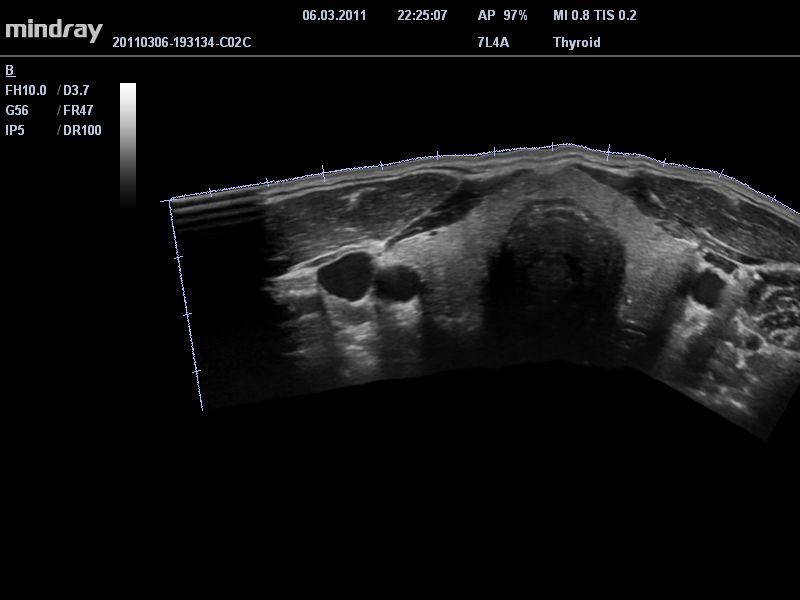

Система сочетает в удобном и компактном корпусе не только традиционные возможности современного УЗИ-сканера, но и инновационные технологии, повышающие точности диагностики состояния пациентов.

• Режимы сканирования: B/M/CFM/PDI/Направленный PDI/PW, HPRF, Тканевая гармоника, М- и цветной М-режим.

• THI со сдвигом фазы: увеличивает четкость визуализации желчного и мочевого пузыря и повышает отношение сигнал-шум.